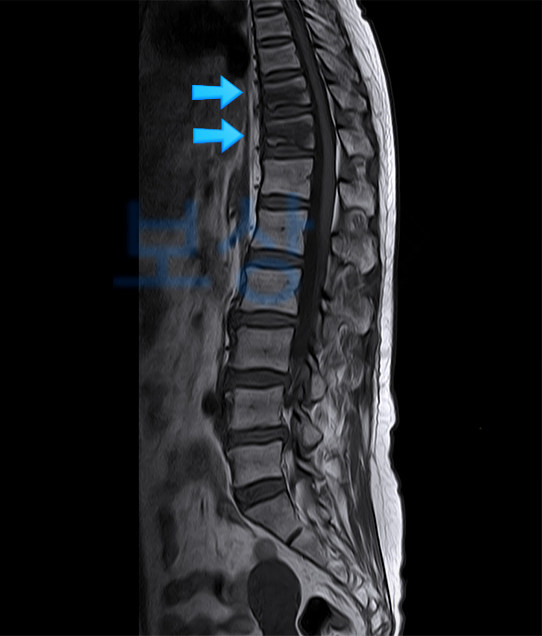

일반적으로는 X-ray 영상 만으로 확인이 가능하나, 특히 경추, 흉추, 요추 부위에 발생한 척추 부러짐은 CT나 MRI 등의 정밀 검사를 통해 정확한 진단명 확인이 필요한 때가 많습니다.

경추, 흉추, 요추 :

수술을 받지 않고 보존적 치유했어도, 뼈의 변형은 영구적으로 남아있기 때문에 후유장애 요건에 해당합니다.

50대이신 김△△ 님께서는 자택 화장실에서 넘어지면서 등뼈를 다치시고, 통증 때문에 급하게 구급차를 불러 내원하셨습니다.

흉추 10번 및 11번 압박골절

[S22060, S22070]

김△△ 님은 약 2개월간 TLSO 척추보조기 착용한 채로 자연적 치유 방법으로 회복하셨는데요. 이후 진단비 및 후유장애 청구 관련하여 저희 사무실에 문의를 주셨고, 면담 끝에 사건을 맡겨주셨습니다.

까다로운 후유장해 진단서 발급부터 보상 담당자와의 지급률 분쟁까지 전반적인 과정을 모두 지원하였고, 고객께서는 회복에 전념하실 수 있었는데요. 최종 결과로 김△△ 님께서는 5대 골절진단비 30만 원, 후유장해 보상 3,000만 원을 수령하실 수 있었습니다.